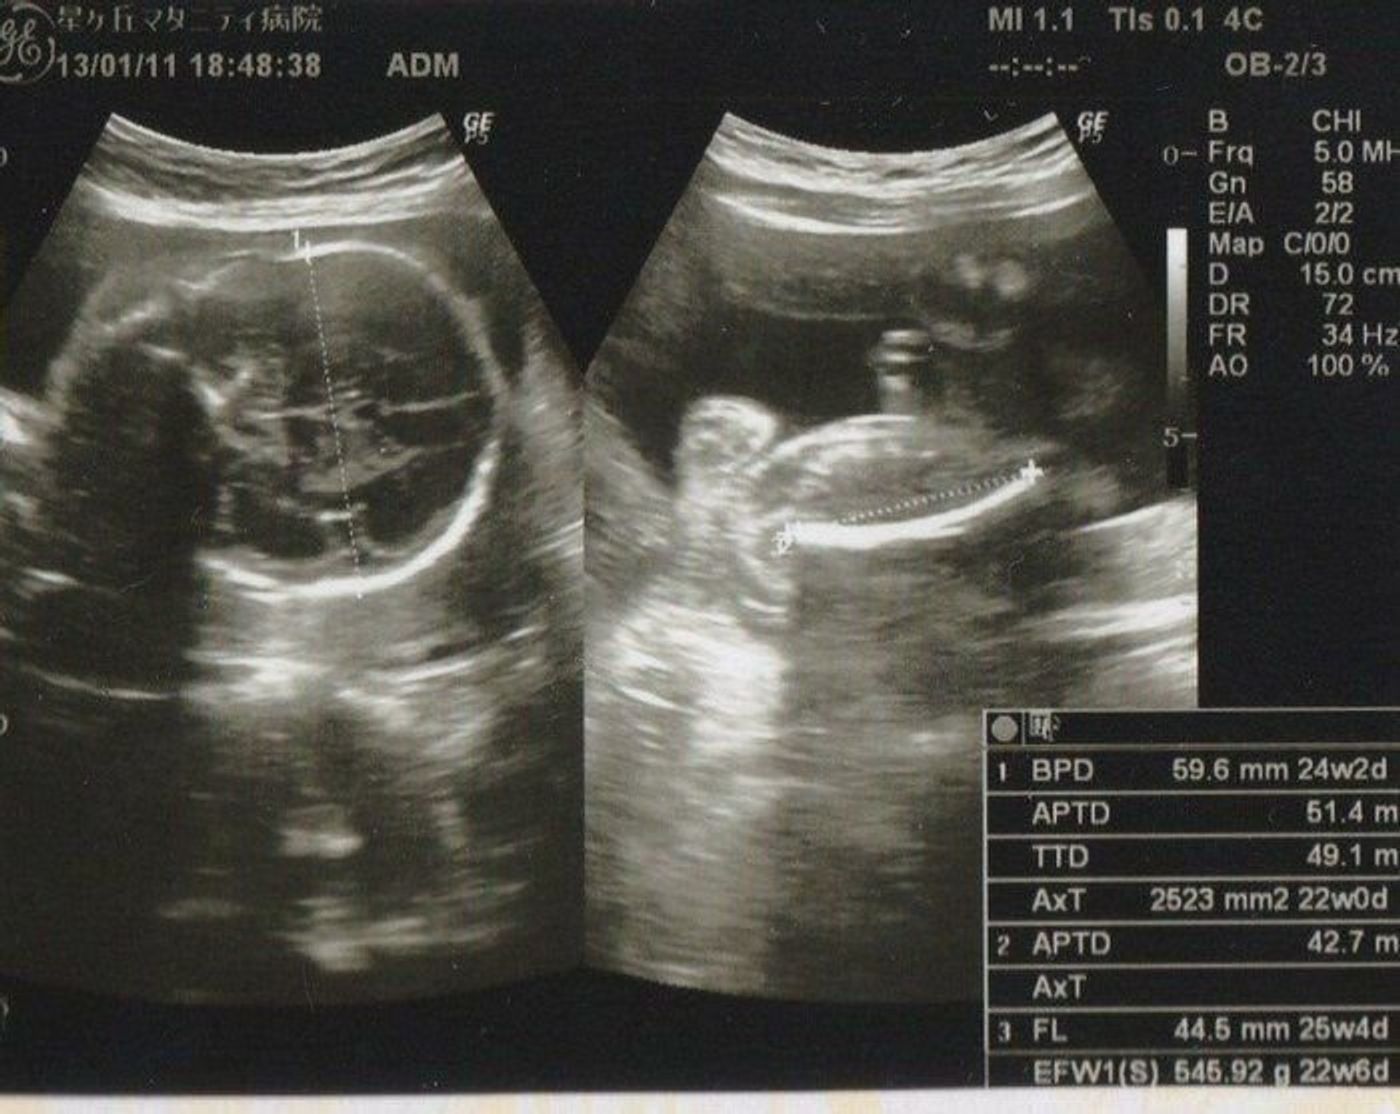

25週3日 エコー-妊娠週 25w3d BPD643cmFL432cm4gの男の子 (^^) 3日程小さいと言わたけど問題も何もなし☆ 子宮底長23cm腹囲80cm お顔が今までの検診で1度も見えたことがありません。 毎回背中しか見5 hours ago 前走の1週前よりはある程度動かしました。 シルクロードsテイエムスパーダ ハンデ気にせず 陣営「2、3番 23年1月25日 0527

25週3日 エコー

妊娠25週3日 25w3d の超音波 エコー 写真